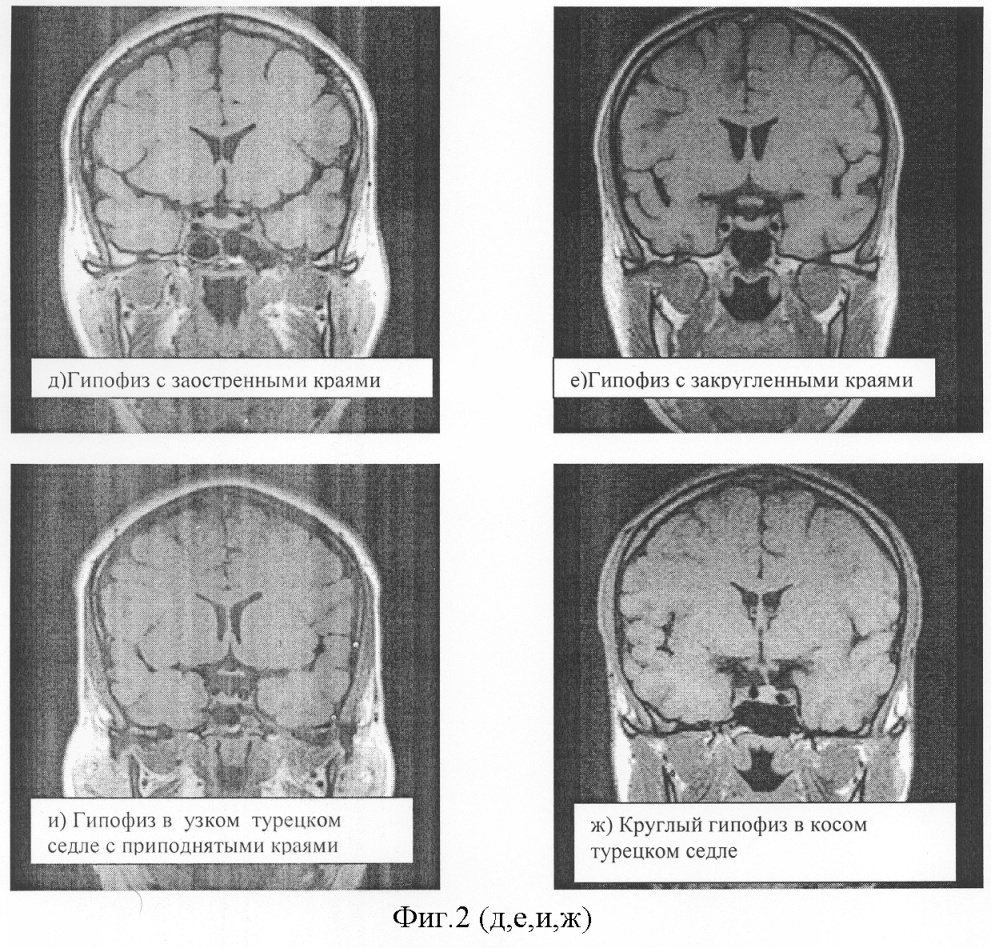

Особенно часто такая ошибка расчета возникает в случаях широкого или узкого турецкого седла и измененных формах гипофиза (фиг.1). Такая ошибка возникает при косом расположении гипофиза, приподнятом одном или обоих краях, возвышающемся левом или правом крыле гипофиза или их разнонаправленности, а также в случаях аденом гипофиза, имеющих разнонаправленный фестончатый рост. В этих ситуациях объем гипофиза, рассчитанный по формуле V=1/2·H·W·L, будет сильно определяться местом измерения параметров высоты, ширины или длины. Существуют варианты гипофиза, когда латеральный размер вообще трудно выделить (фиг.2).

Ниже схематически представлены наиболее часто встречаемые формы гипофизов по фронтальным сечениям (фиг.1), при расчете объема которых по формуле Di-Chiro Nelson возникает ошибка измерения, иногда достигающая 30 и даже 50%. Разнообразие форм гипофиза, как правило, определяется формой турецкого седла, варианты строения которого зависят от формирования и развития костей черепа. Далее приведены в качестве иллюстраций томограммы гипофизов во фронтальных сечениях (фиг.2).

На фиг.1 схематически показаны наиболее часто встречаемые формы гипофизов, расчет объема которых по формуле Di-Chiro-Nelson дает максимальную ошибку. Цифрами на фигуре обозначено: 1, 2 – наиболее часто встречаемые варианты нормы; 3, 4, 5 – пубертатные гипофизы; 6-11 – гипофизы в широком турецком седле; 12 – гипофиз с фестончатыми краями; 13, 14 – круглый гипофиз и гипофиз в узком турецком седле; 15-16 – форма гипофиза в пустом турецком седле.

На фиг.2 представлены магнитно-резонансные томограммы вариантов гипофиза, полученные во фронтальных сечениях. При этом на фиг.2а показан гипофиз в узком турецком седле; 2б – круглый гипофиз в косом турецком седле; 2в – корытообразный гипофиз в косом турецком седле; 2г – гипофиз с уменьшенным правым крылом; 2д – гипофиз с заостренными краями; 2е – гипофиз с закругленными краями; 2и – гипофиз в узком турецком седле; 2ж – гипофиз в косом седле; 2з – корытообразный гипофиз в косом седле; 2к – гипофиз с уменьшенным правым крылом; 2л – гипофиз с приподнятыми крыльями; 2м – гипофиз в пустом турецком седле.